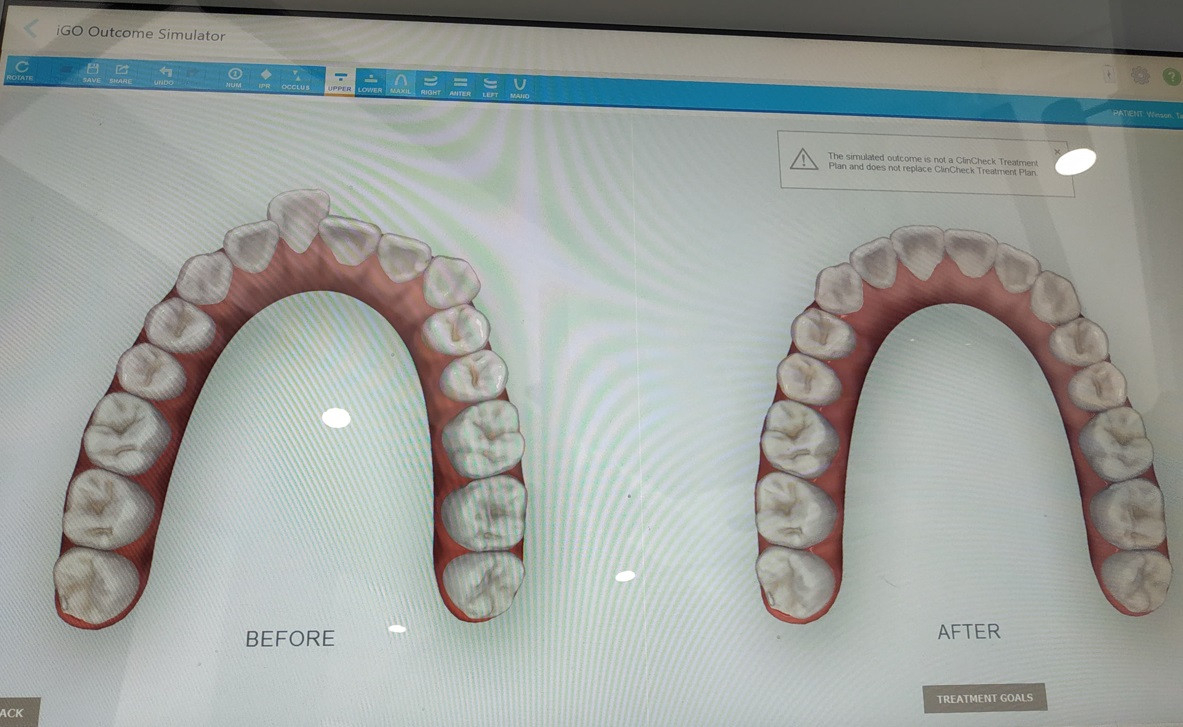

Already did the free consultation and they use iTero scanner and I can see the simulation instantly. Since my case is mild and would most likely take 5 months to complete. So far I am satisfied with the 'after' simulation result.

Yea I think it is mild also but actually last year I went to another Invisalign dentist and she said mine will take almost 2 years because I need to pluck 2 teeth behind and she thinks it was serious. Luckily the recent 2 dentists think my one is mild (I posted my "before" pics below)

user posted image